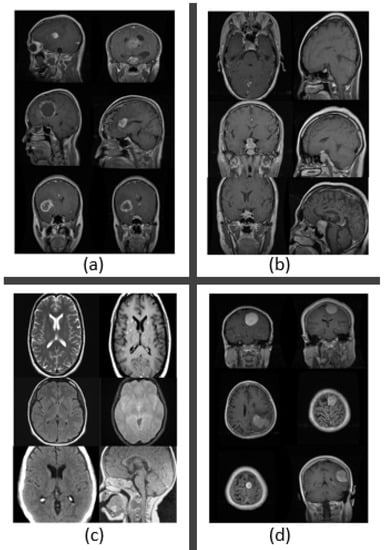

3.3. Dataset Collection

| Brain Tumor Type | Count |

|---|---|

| Glioma Tumor | 926 |

| Meningioma Tumor | 937 |

| No Tumor | 500 |

| Pituitary Tumor | 901 |

| Total | 3264 |